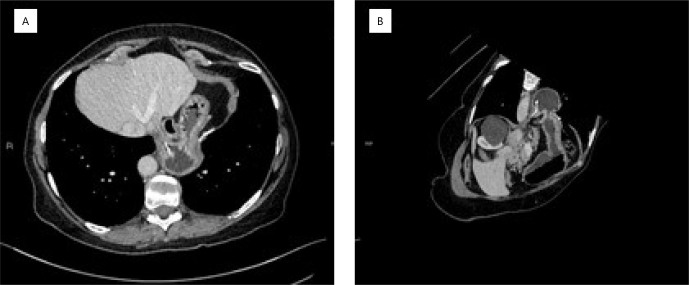

背景:补片在大裂孔疝修补中的应用仍存在争议。与使用补片有关的最可怕的不良事件之一是食管和胃壁的侵蚀。目的:记录裂孔疝手术治疗后胃腔内移位补片的内镜处理。方法:技术方案为等待补片逐步向胃腔内移动,在上消化道内镜下监测,在异物钳辅助下,在最佳时机牵引取出。结果:补片完全取出,进展满意,无并发症。结论:对于无症状且无并发症迹象的补片入胃患者,在补片未粘附胃壁的情况下,可以成功进行内镜监测和随后的异物取出,避免了高发病率和死亡率的手术。

Background: The use of mesh in the repair of large hiatal hernias is still controversial. One of the most feared adverse events related to the use of mesh is erosion into the esophageal and gastric walls.

Aims: To record the endoscopic treatment of mesh that has migrated into the gastric lumen after surgical treatment of hiatal hernia.

Methods: The technical option was to wait for the progressive migration of the mesh into the gastric lumen, monitoring with upper digestive endoscopy, with removal by traction at the best time, with the aid of foreign body forceps.

Results: The mesh was completely removed, and the evolution was satisfactory, without complications.

Conclusions: In patients with mesh migration into the stomach who are oligosymptomatic and do not show signs of complications, endoscopic surveillance and subsequent removal of the foreign body can be successfully performed when the mesh is not adhered to the gastric wall, avoiding surgical procedures with high morbidity and mortality.